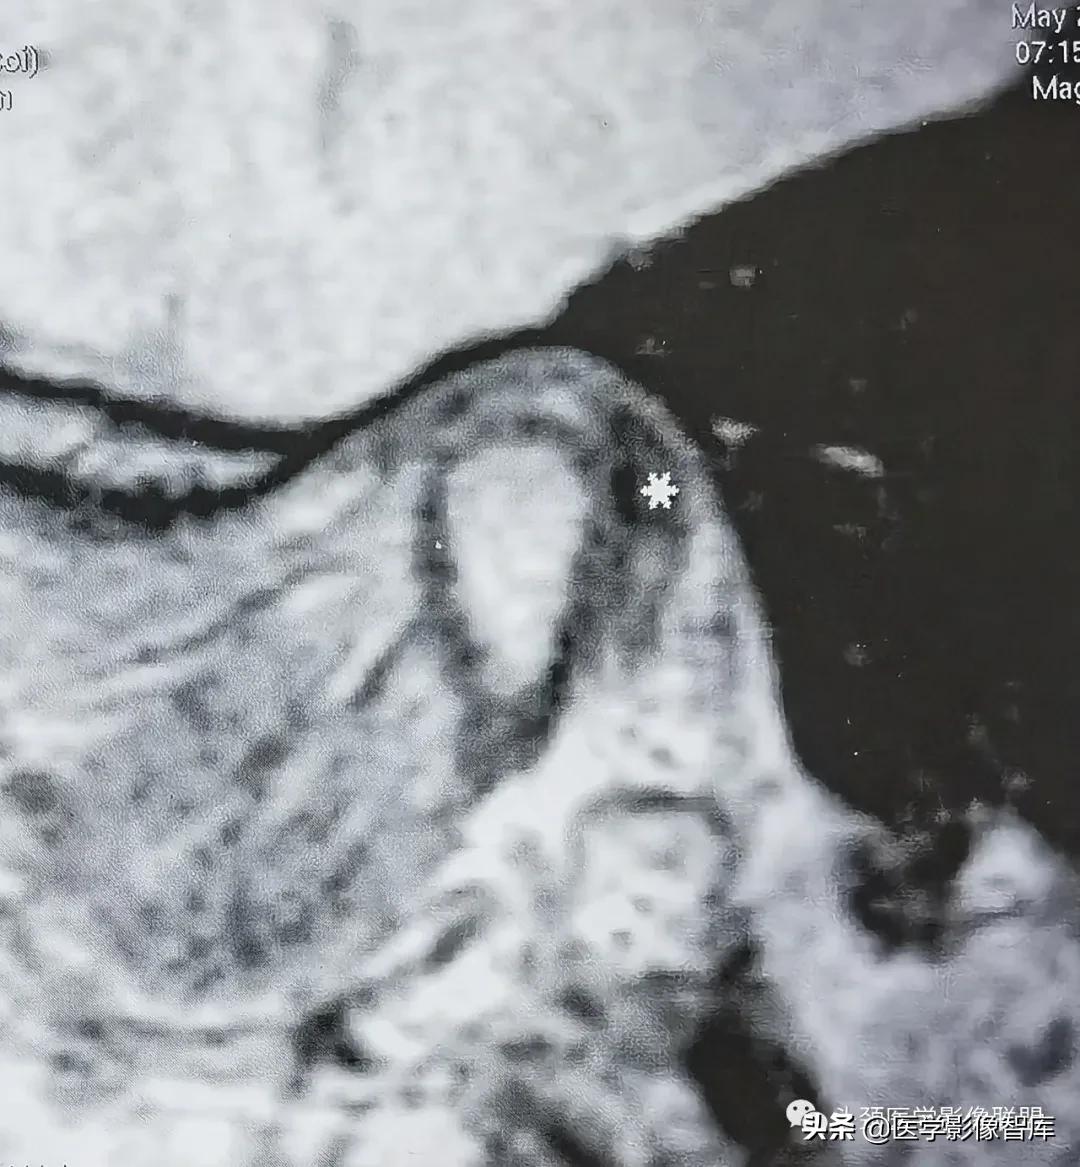

图10-3-8 关节盘后移

矢状面闭口 PDWI示关节盘后带(白星)位于下颌髁突后方。

关节盘后移位是指关节盘的一部分位于下颌髁突之后。盘后移极为罕见。Westesson等统计显示其发生率约为1%。大约50%的关节盘后移伴有关节盘旋转移位。部分患者尚可合并关节盘穿孔。MRI上,如发现关节盘后带位于下颌髁突的后方则可诊断为关节盘后移位 (图8) 。